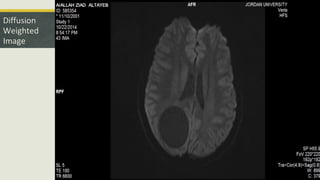

Diffusion

Weighted

Image

 So this is an Intra axial supratentorial parieto-occipital cystic lesion with focal

area of enhancement within its wall, no restricted diffusion, and with some

vasogenic edema.

 1. Not an abscess because the DWI was free from any restricted diffusion.

• #20 no evidence of any restricted diffusion. thus ruling out the possibility that it may be an abscess. Its an intra-axial lesion. so we needed to give contrast to give more diagnostic character into this lesion.

• #23 the adjacent ventricle it is more prominent than the other ventricle, thus opposing the theory of mass effect, and suggests volume loss due to the insult.